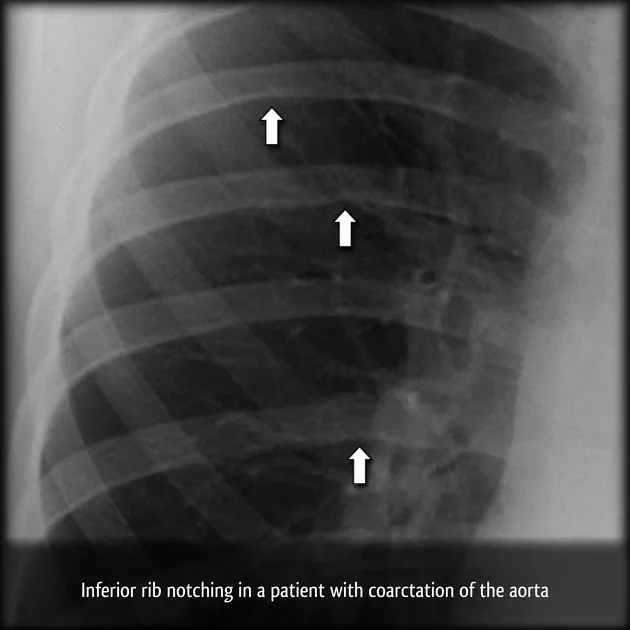

- CXR: "3" sign (aortic knob, coarctation, post-stenotic dilatation), rib notching (inferior, 3rd-8th ribs).

- Coarctation of Aorta: Rib notching (inferior, posterior ribs 3-8); "3" sign on barium/aortogram.